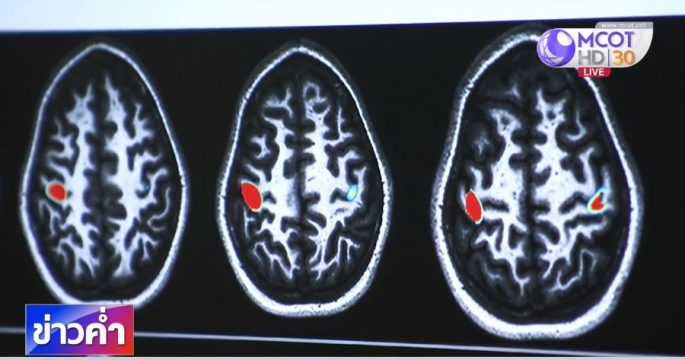

ยังคงถกเถียงกันไม่จบสำหรับการแก้ไข พ.ร.บ.กีฬามวย ที่ยังมีทั้งเห็นต่างและเห็นด้วยถึงเกณฑ์อายุที่เหมาะสมให้เด็กขึ้นชกอาชีพ ในด้านสุขภาพการกระทบกระเทือนทางสมองตั้งแต่อายุยังน้อย จะส่งผลอย่างไรกับร่างกายบ้าง